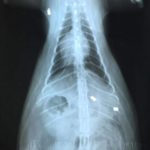

Strona główna Ktoś strzela z wiatrówki do zwierząt przych wet 1

przych wet 1

przych wet 2